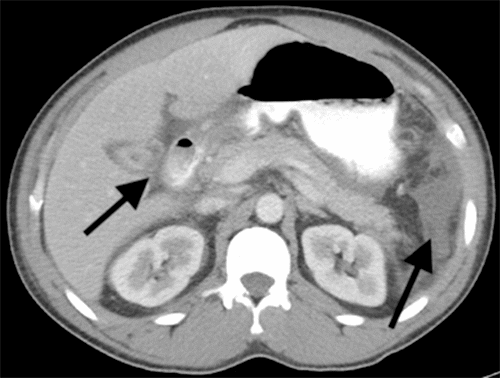

While the patient reported initial relief of symptoms within 48 hours of the initial procedure, he experienced a recurrence of nausea, distension, and abdominal pain. Post paracentesis, CT imaging of the abdomen pelvis failed to show extravasation of oral contrast from viscera (Figure 1) but revealed a contracted gallbladder and re-accumulation of ascites. A hepatobiliary iminodiacetic acid (HIDA) scan showed a biliary leak from the region of the gallbladder fossa (Figure 2). Magnetic resonance cholangiopancreatography showed recurrent ascites but no biliary obstruction (Figure 3). No traumatic injuries were identified on the initial imaging. Repeat paracentesis yielded one liter of bilious fluid, again with a resolution of symptoms.

Figure 1. CT Abdomen and Pelvis with Oral and Intravenous Contrast Showing Ascites and Contracted Gallbladder (arrows). Published with Permission